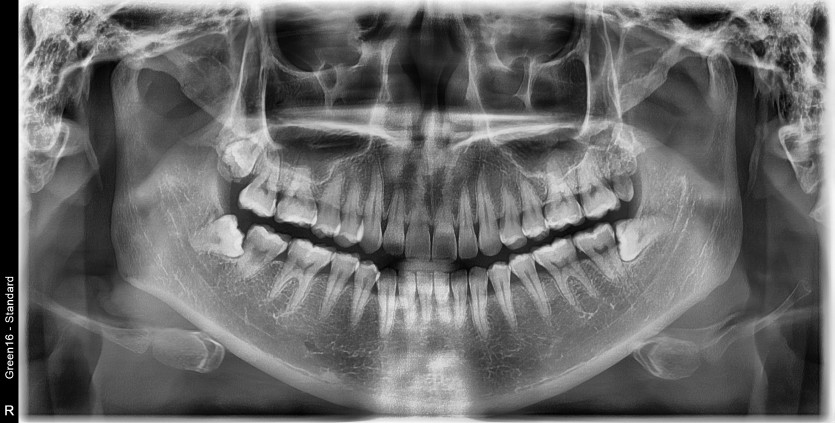

#38 사랑니 발치

구강 외과 전문의가 당일 발치했습니다.